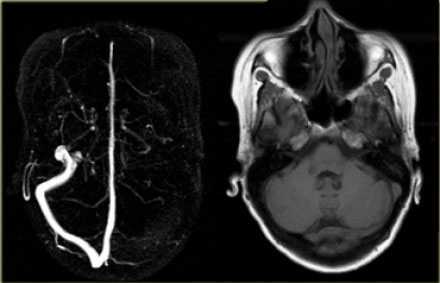

Тромбоз правого поперечного синуса - гипоинтенсивные участки по Т2 (внутриклеточный дезоксигемоглобин).

Для подтверждения тромбоза венозного синуса и определения точной локализации и протяженности тромба необходимо проведение МР-венографии.

МР-венография - отсутствие визуализации кровотока в правом поперечном синусе и яремной вене.